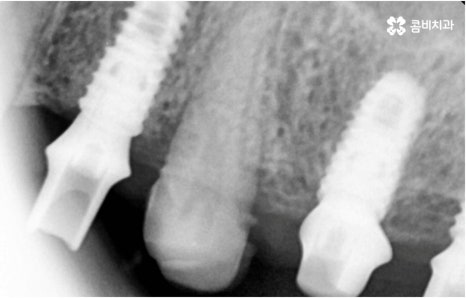

자연 치아를 살리기 위한 거의 마지막 단계의 보존 치료가 바로 신경치료, 재신경치료, 치근단절제술 등이며, 만약 치아재식술을 통해서도 살릴 수 없을 정도로 손상이 깊고 심하다면 해당 치아를 발치하고 임플란트를 통해 인공 치아로 대체해 줄 필요가 있습니다.

임플란트는 유치, 영구치 이후로 제 3의 치아라고 불리울 만큼 자연 치아의 상실에 대처하는 인공 치아 중에 가장 각광을 받고 있습니다. 저작력 회복이 80%에 가깝고 심미적으로 자신의 치아와 거의 다름없어 보이는 부분에서도 만족도가 높아 많은 분들이 찾고 있지만 식립 성공률과 안정적인 지속률에 크게 영향을 주는 올바른 위치 및 각도로의 식립을 무리하지 않게 진행하기 위해 술자의 높은 숙련도를 요하는 고난도의 수술이기 때문에 임상 경험이 많고 뛰어난 노하우를 갖추고 있는 담당의 선생님과 함께 하시는 것이 중요한 포인트라고 할 수 있어요.

환자분들의 상황에 따라 하루 만에 식립 및 임시 치아 장착까지 끝나서 바로 식사를 할 수 있는 원데이 임플란트 과정, 정밀 검사 후 디지털 장비를 이용하여 모의 수술 후 맞춤 가이드를 따라 무절개 / 최소절개 수술을 진행하는 네비게이션 임플란트 과정 등 관련 기술이 점점 더 섬세하게 발달하고 있어서 보다 편안한 이용이 가능하게 된 것은 사실이지만 본래 자신의 치아보다 좋은 인공 치아는 없을 것이기 때문에 건강할 때 이를 잘 유지 관리하고 구강 질환이 발생했을 때는 되도록 빠르게 이에 대처하실 필요가 있어요.